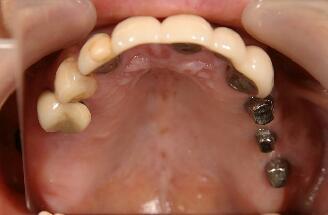

最終かぶせ物(メタルボンドポーセレン)を装着した口腔内写真

このあと右上上顎(上の写真では左の上となります)のインプラントを予定している

予定通り4ヶ月で最終かぶせ物(メタルボンドポーセレン)を装着

この症例も十分咬合に耐える、しっかりした骨が形成されています